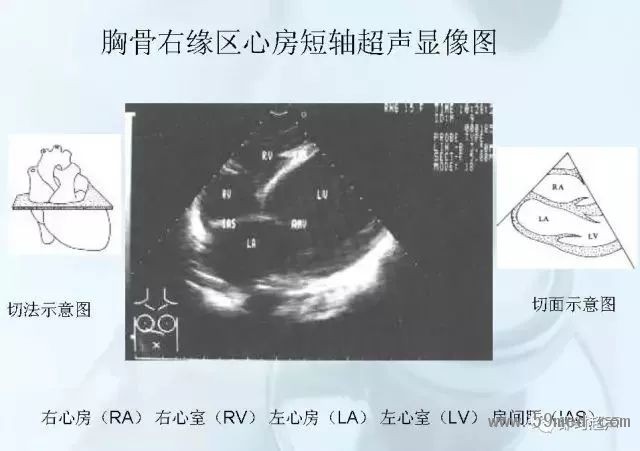

![]() ![]() ![]() ![]() ![]() ![]() ![]() ![]() ![]() ![]() ![]() ![]() ![]() ![]() ![]() ![]() ![]() ![]() ![]() ![]() ![]() ![]() ![]() ![]() ![]() ![]() ![]() ![]() ![]() ![]() ![]() ![]() ![]() ![]() ![]() ![]() ![]() 【注:本文來源于即時超聲,版權(quán)歸原作者所有,如有侵權(quán) 請聯(lián)系 速刪】 =========================== 【閱精彩*悅分享】隨手點擊轉(zhuǎn)至朋友圈,與大家一起分享精彩資訊!當(dāng)然您也可以通過以下方式找到我,與您共同分享藍(lán)韻影像超聲的更多精彩!微信號:landultrasound 電話:+86-0755-66869896 24小時客服熱線:400-888-6452